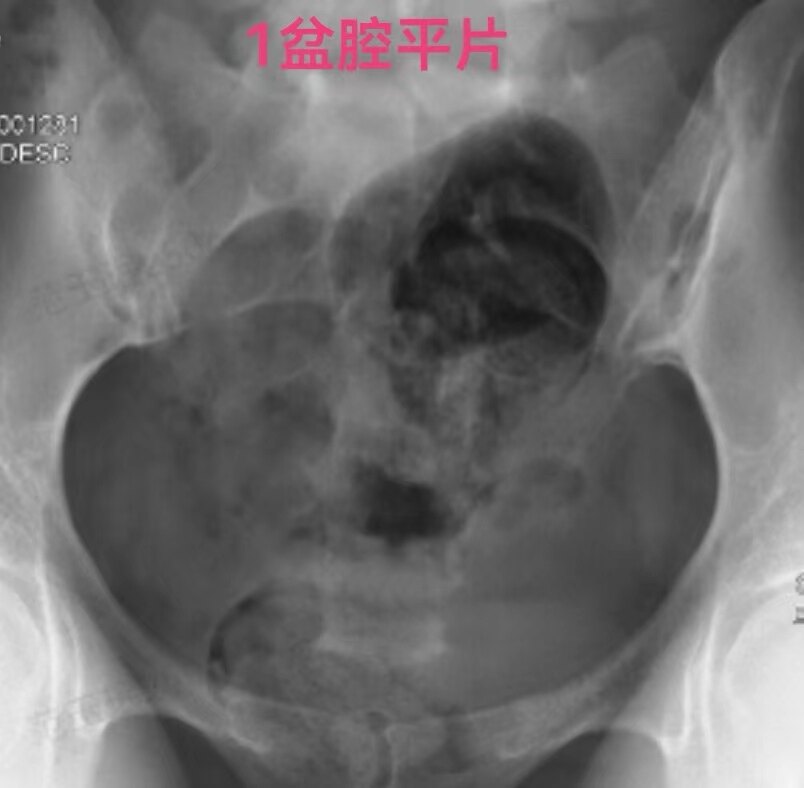

在做子宫输卵管造影检查时:当所用造影剂为碘油,出现静脉和淋巴管逆流时,立即停止造影检查是对的。因为碘油和血液不能相容混合一起,碘油会形成油栓。因此,当碘油进入静脉和淋巴管后会进入下腔静脉,进入右心房,进而进入肺动脉,形成肺栓塞,可危机被检查者生命安全。但是,当所用造影剂为碘水,出现静脉和淋巴管逆流时,可以继续造影检查,直至满足临床诊断后再结束检查。因为碘水和血液可以相容会混合一起,碘水逆流进入静脉和淋巴是安全的。大家好多做过CT增强检查,成年人一般需要用高压注射器要向静脉内快速注入100毫升碘水进行检查,都是安全的。造影注入10毫升左右碘水,即使都进入静脉也没事。这二例,一例碘油造影是一大学附属妇产医院做放射科的,该立即停止造影却没有停止。万幸,逆流进入静脉的碘油少,没有造成严重后果。另外一例碘水造影是一省妇幼保健院放射科做的,不该停止造影检查,反而停止造影检查,未能完成检查,不能给正确诊断。

第一例碘油造影图和报告单